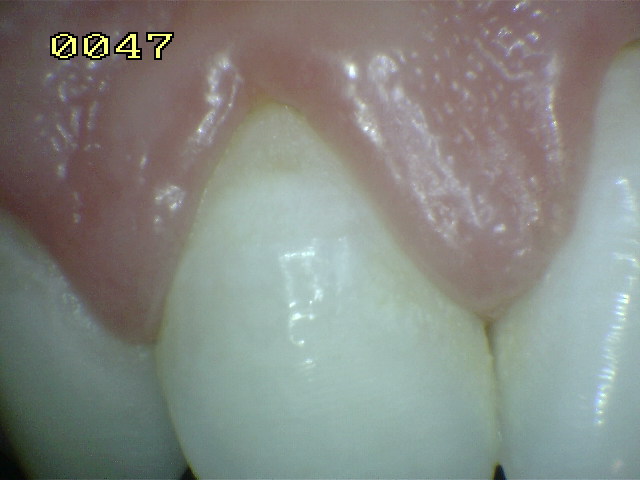

Encía Normal |